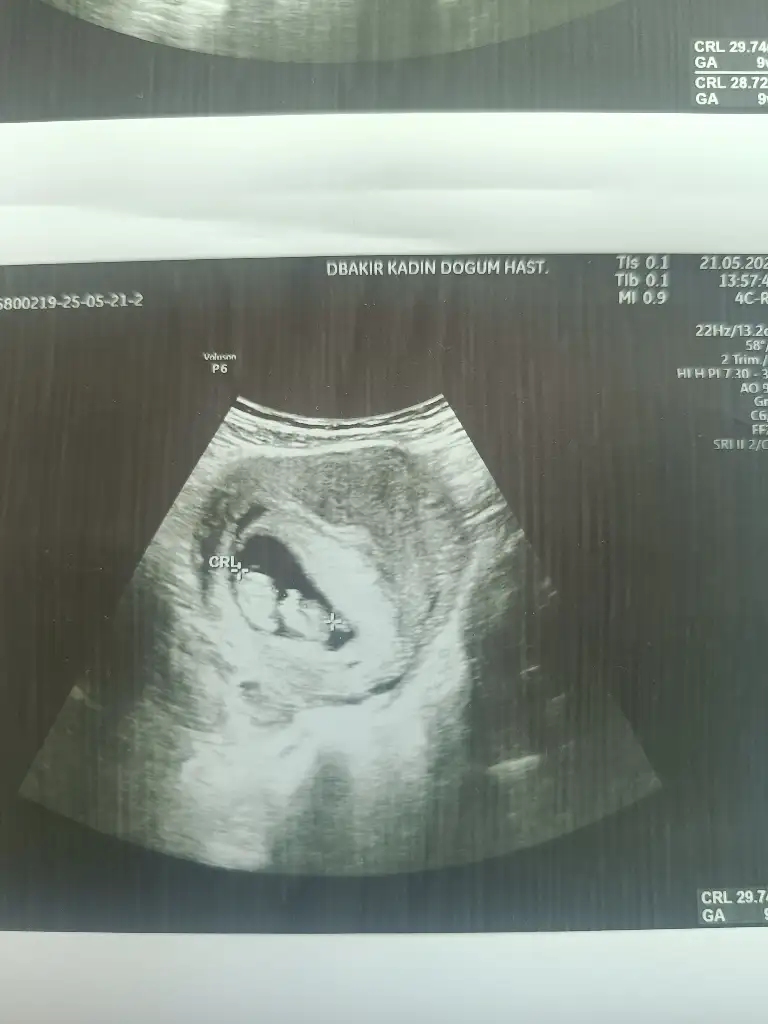

Bana da bakar mısınız bu 8+2 karın ultrasonu

Eklentiler

• IMG_2019.webp

27,5 KB · Görüntüleme: 23